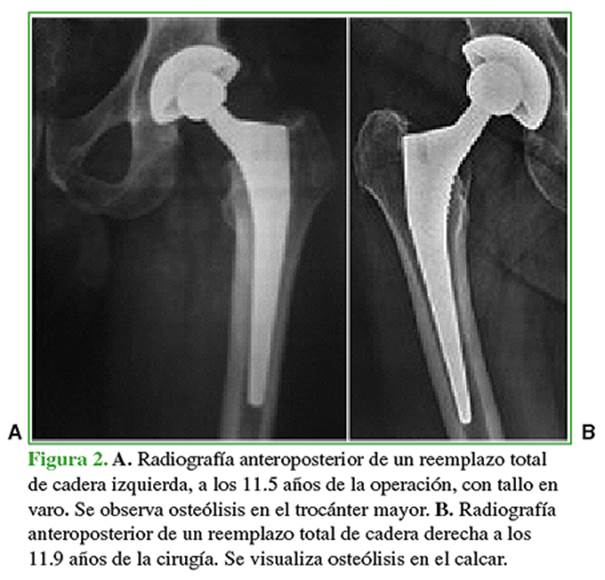

Se observó osteólisis femoral proximal en dos pacientes (3,0%): un tallo con un varo de 2º en el trocánter mayor, con un seguimiento de 11.5 años, y en otra cadera con varo de 3º en el calcar, con 10.9 años de evolución (Figura 2). En ambos, no hubo complicaciones ulteriores ni evidencia de progresión radiográfica.